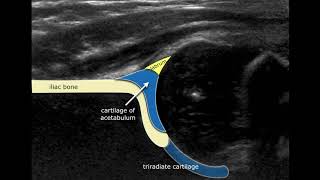

Congenital Hipdysplasia - Ultrasound Anatomy

83.371

0:42

Hip Ultrasound

127.583

8:53